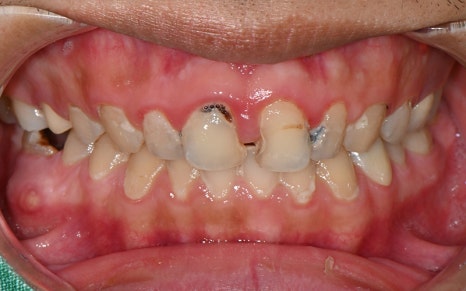

💛 First Visit 💛

The patient we are introducing had several cavities in progress,

and the pain would come and go,

which made it even easier to miss the right timing for treatment.

Looking at the before-treatment photos,

the front teeth had large cavities and damage

to the point that it was hard to smile,

and the areas filled with resin here and there

were also a major source of aesthetic stress.